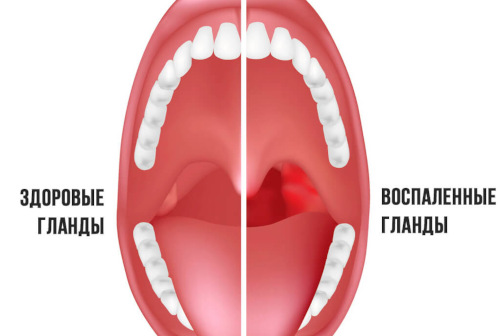

TONSILLECTOMY

. . These are three completely different surgical procedures, so they should not be confused. Tonsillotomy and tonsillectomy operations have the following differences: Tonsillotomy is a partial resection of lymphoid tissue, which is aimed at removing the ...

ADENOTOMY

. . At the early stages of the pathology, the doctor prescribes conservative treatment - physiotherapy and medication. Surgery is necessary if drug therapy has not yielded results. Indications for surgery are determined by the doctor at the appointment! ...